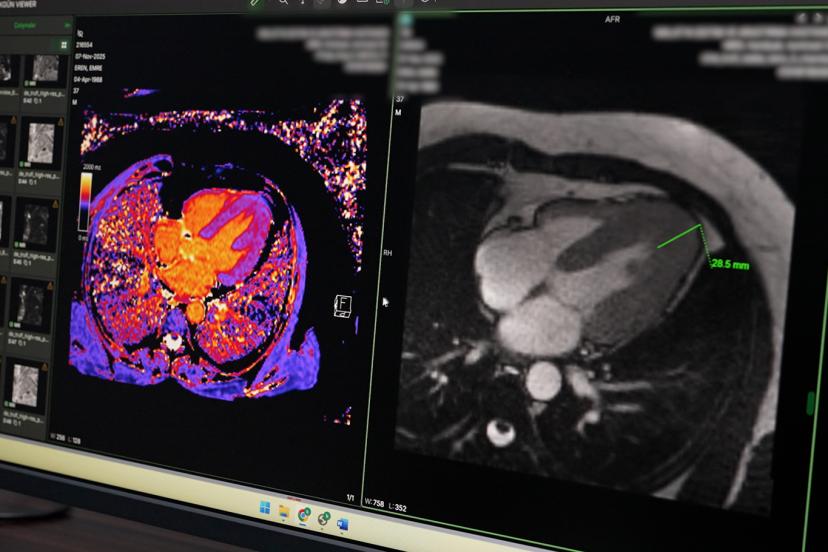

Hastanede yeni başlatılan önemli uygulamalardan birinin de kardiyak MR olduğunu ifade eden Doç. Dr. Petik, bu yöntemin günümüzde kalp kası hastalıkları, kapak hastalıkları ve damarsal anomalilerin değerlendirilmesinde dünyada ön sıralarda yer aldığını söyledi. Kardiyak MR sayesinde kalp kası yapısının detaylı olarak incelenebildiğini belirten Petik, birçok hastalığın tanı ve tedavi planlamasının artık bu görüntüleme yöntemi üzerinden yapıldığını ifade etti.

Açıklamalarında örnek bir vakaya da değinen Petik, 35-40 yaşlarında erkek bir hastanın kalp yetmezliği şikâyetiyle kendilerine yönlendirildiğini belirtti. Yapılan kardiyak MR incelemesinde hastanın sol ventrikül duvar kalınlığının yaklaşık 30 milimetreye ulaştığının tespit edildiğini ifade eden Petik, bu durumun hastanın yaşam kalitesi ve performansını ciddi şekilde etkilediğini söyledi.

Söz konusu hastalığın klasik anjiyografi ile anlaşılmasının mümkün olmadığını belirten Petik, ancak ileri kardiyak görüntüleme yöntemleriyle tanı konulabildiğini vurguladı. Hastaya Yamaguchi Sendromu olarak bilinen özel bir kalp kası hastalığı tanısı konulduğunu söyleyen Petik, erken tanı sayesinde uygun tedavi planlamasının yapıldığını ve ilerleyen dönemde oluşabilecek ciddi kalp yetmezliği riskine karşı önlem alınabildiğini ifade etti.